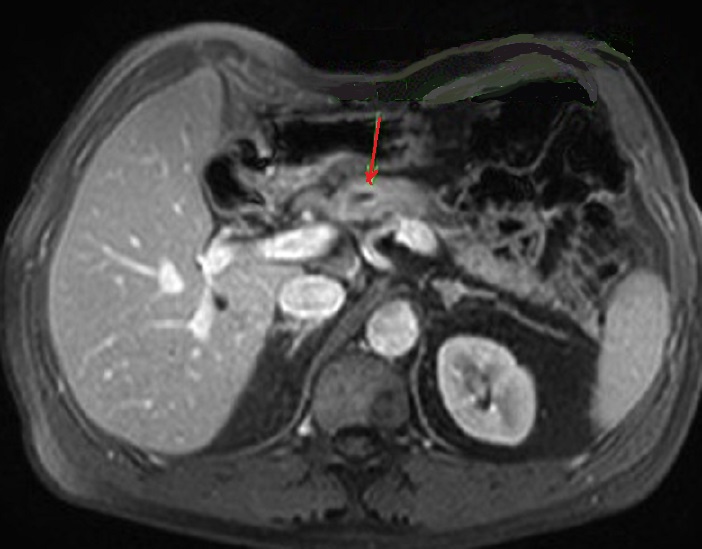

Image radiologique TDM de

evolution malignite d'une TIPMP de type canal

principale avec aspect lesionnel de dilatation ,

epaissisement et de rehaussement de sa paroi (

fleche rouge ) |